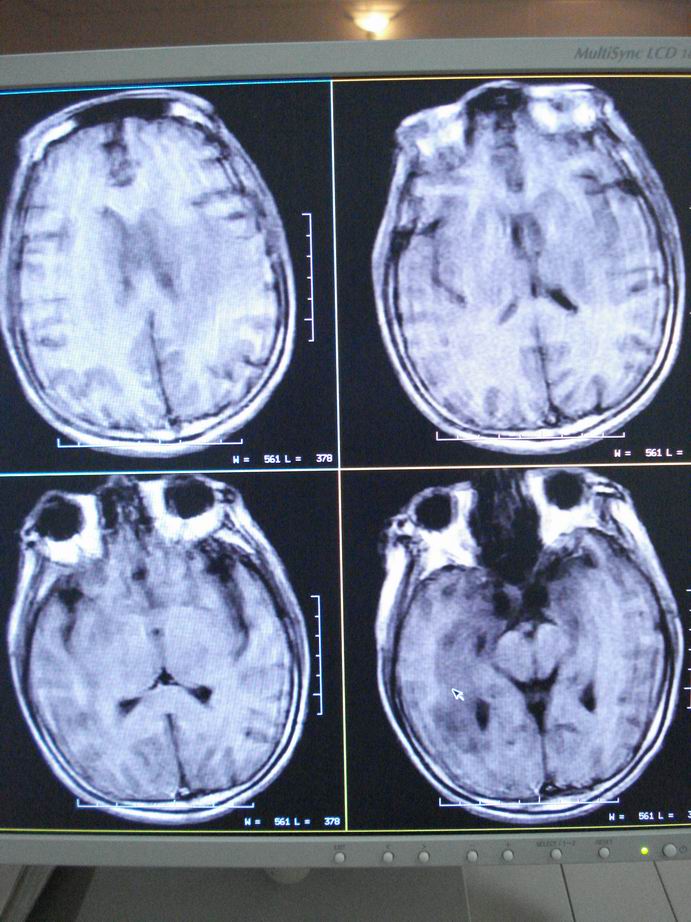

男60岁,左侧肢体乏力及精神异常10天,血压正常,血常规,肝肾功正常,腰穿无异常,请教颅内多发病灶,考虑什么?感染?肿瘤(转移性?)还是其它?

考虑为颅内多发转移瘤

脑内多发性转移瘤。

淋巴瘤较转移瘤可能大。

脑内多发占位性病变,首先考虑感染性病变,其次是转移瘤。

结合病人高龄,考虑转移瘤